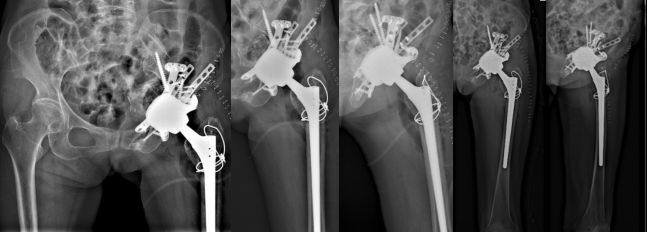

针对髋臼骨缺损严重、慢性骨盆不连续,目前的假体无法重建髋臼、无法获得稳定固定,拟采用3D打印技术定制特殊髋臼假体重建髋臼,在此基础上,左侧髋关节翻修的手术的后外侧入路进入,取出髋臼假体,植入根据患者髋臼骨缺损情况个体化定制的3D打印髋臼假体,进行左侧全髋关节翻修手术。

图 术前手术规划与个体化假体设计

手术成功,术后3天下地行走

7月4日,由麻醉手术中心杨静教授团队麻醉,在手术室护理团队的精密配合下,康鹏德教授与马玉奎教授团队联合展开手术。术中仔细游离左侧髂动脉及原髋臼周围粘连的软组织,经过紧张、惊险的分离取出等一些列过程,3小时后,手术顺利完成。

术后患者平安返回病房,在医护团队的精心护理、治疗及康复指导下,术后恢复顺利,7月5日,手术第一天即扶助行器逐渐下地行走,并于7月8日顺利出院。目前患者康复髋关节功能良好,在助行器辅助下患肢负重活动,预计几周后可脱离辅助逐渐自由行走。

此例手术为华西医院第3例由关节外科与血管外科团队共同手术进行突入骨盆髋臼假体的高难度翻修手术。也是康鹏德教授团队采用3D打印定制化假体进行严重髋臼骨缺损重建的第16例患者,是华西多学科团队协作MDT技术的再一次体现,也为华西在关节置换高难度翻修领域中进一步积累了宝贵经验。